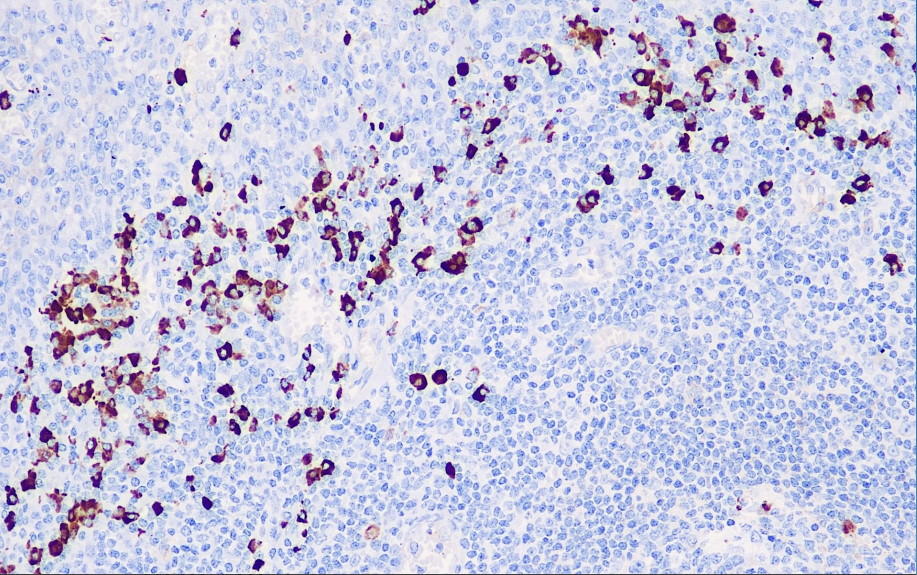

Cellular localization: cytoplasmic

Positive control: tonsils

This antibody reacts with the λ light chain of human immunoglobulin and has no cross-reaction with the κ light chain. B lymphocytes and plasma cells with λ light chains can be studied. The extracellular immunoglobulin λ light chains can also be stained, and it should be noted to distinguish them. The research suggests that the common feature of B lymphocyte tumors is that they are limited to the expression of a single light chain. Therefore, κ and λ light chains can be used in the study of benign and malignant lymphocytic lesions (reactive lymphocytic hyperplasia and lymphoma).

Lambda antibody reagents can specifically bind to Lambda antigens. Immunohistochemical kits containing Lambda antibody reagents are suitable for the precise diagnosis of benign and malignant lymphoid lesions.